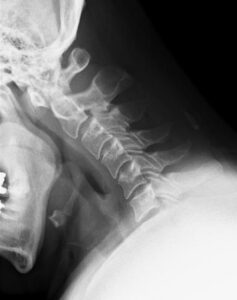

ムチウチの正式名称は外傷性頸部症候群、または頚部捻挫といいますが、腰の捻挫をギックリ腰というように、首の捻挫を頚部捻挫、つまりムチウチといいます。

強い衝撃を体に受けることで、頭がおもりとなって首が鞭のようにしなることからムチウチと呼ばれており、事故にあったその時はなんともなく、1〜2日経ったあたりから症状が出はじめます。

症状としては首や肩の痛み、しびれ、頭痛、耳なり、めまい、吐き気、肩コリ、食欲不振、手足のしびれ、感覚異常、倦怠感、ふらつき、排尿障害などが起きます。

5.頚椎の歪み:

頚椎の歪みによる筋肉や血管の緊張や圧迫

腰はその下に脚しかありませんが、首の下は頭以外の体の全てがあるので、首の損傷は全身に支障をきたします。

また、腰と違い首は細くて筋肉が少ないにも関わらず重い頭をのせています。

さらに頭には脳が入っているため、常に敏速な反応ができるように関節の可動域や柔軟性もあるので障害も受けやすくなります。